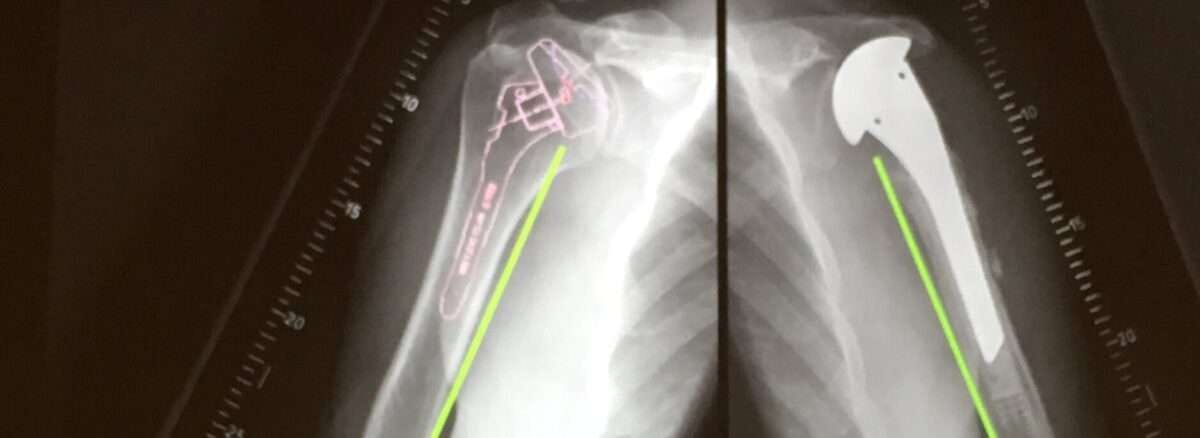

- Shoulder

- Shoulder.